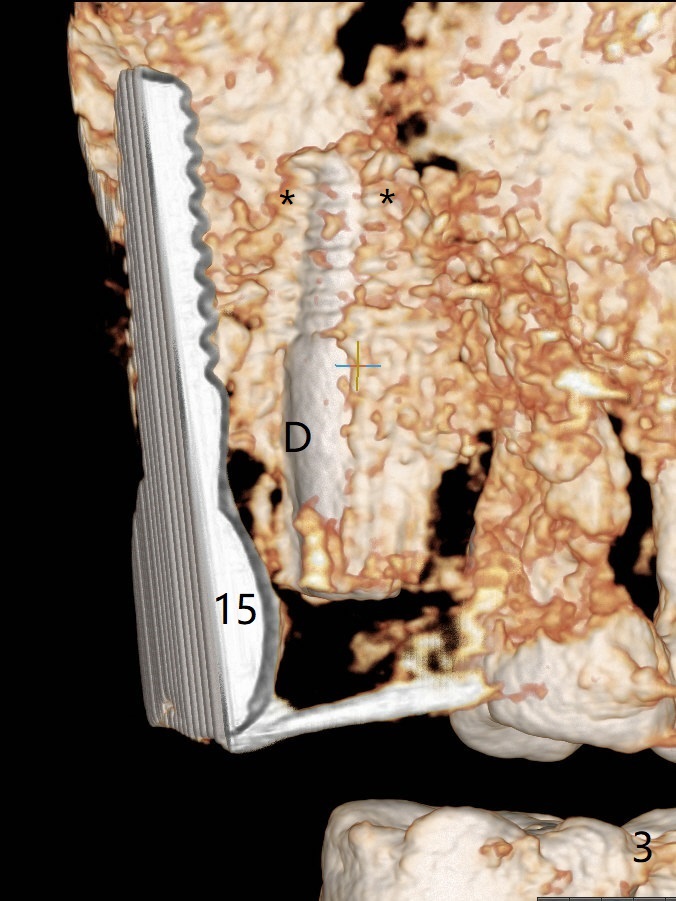

After osteotomy with guide at #14 (4.5x7.3 mm last drill with 1 O-ring/10.5 mm offset for bone-level implant), a 5x11 mm tissue-level tap is used with allograft for sinus lift (Fig.1). With one more round of allograft for sinus lift, a 5x11 mm tissue-level implant is placed with ~ 50 Ncm (Fig.2). CBCT 3-D images (Fig.3 (palatal view), 4 (distal view) (D: distal)) and coronal section (Fig.5 (P: palatal)) show the bone graft in the sinus (*). The patient returns for restoration 5 months postop in spite of running out insurance benefits because of discomfort with the immediate provisional. When the latter is removed (Fig.6), the gingiva is erythematous. It appears that the implant was placed deep. The abutment is removed for easy local oral hygiene. A healing cuff will be used or the implant will be reversely torqued. If the former is placed, a 4 mm longer abutment (4.5x9 mm) should be used to increase crown retention using temp bond . In fact the provisional forms a nice gingival cuff before cementation (Fig.7,8). Return to Upper Molar Immediate Implant, Prevent Molar Periimplantitis (Protocols, Table), Trajectory 18 Xin Wei, DDS, PhD, MS 1st edition 04/22/2019, last revision 02/28/2020